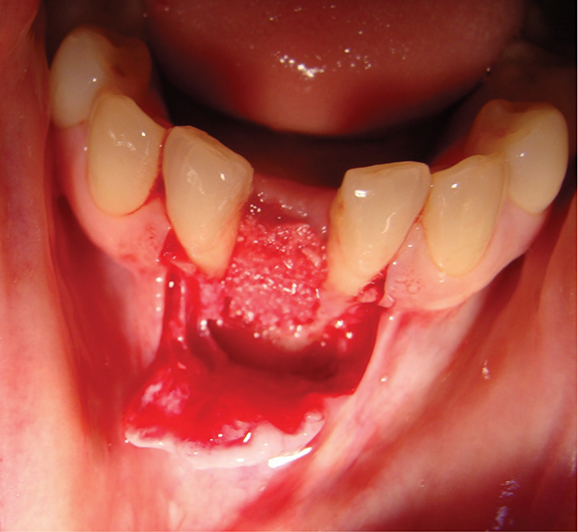

Above: Guided bone regeneration using a particulate anorganic bovine graft in the lower incisor area.